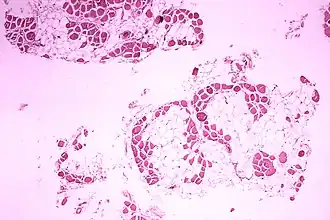

Требуется лабораторная диагностика[4] — обычно речь идёт о биопсии мышечной ткани и генетическом исследовании. Но на первых этапах диагностики достаточно теста КФК, это главный биохимический маркер миодистрофии Дюшенна. У мальчиков с Дюшенном повышен в десятки или сотни раз.[1]